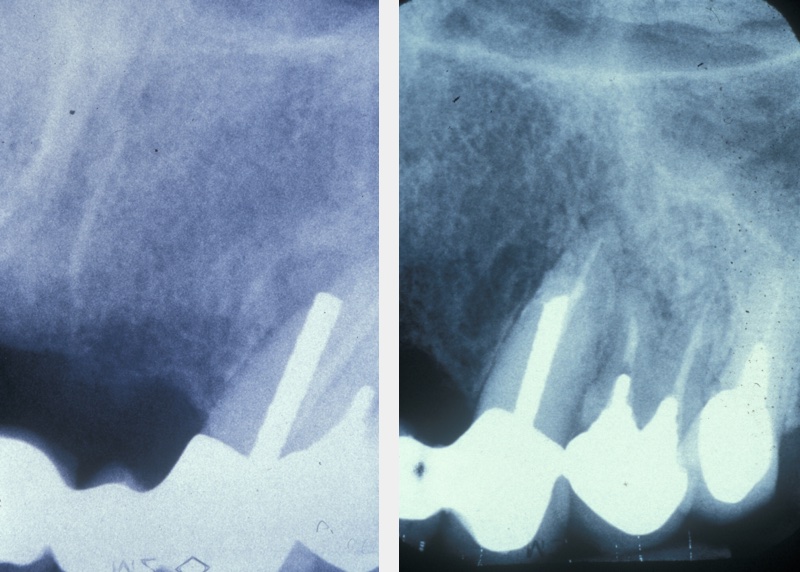

Assessment for endodontic surgery

A medical history, clinical examination, and radiological examination should be performed when surgical endodontic treatment is being considered. Where applicable, previous conventional endodontic treatment (root canal treatment) is also assessed and a decision made on its effectiveness. Local anatomical factors, such as the proximity of the surgical area to the maxillary sinus (cavity above the upper jaw) or neurovascular bundles (important nerve and blood vessel structures) need to be taken into account, as does the feasibility of surgery. Figure 1 gives an example where periapical surgery was the preferable option over conventional treatment.